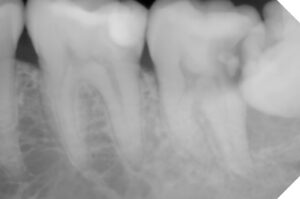

同年1/15 薬液除去し最終パッキング材で蓋をし

土台を作成する型取りをして仮詰めで終了

1時間半の工程で自費: 19500円+リーマ代2800円

同年1/29 できてきたファイバーコアの土台をset

レントゲンでは神経の詰め物の状態の違い→

歯根の崩壊度は経時的なもの?→